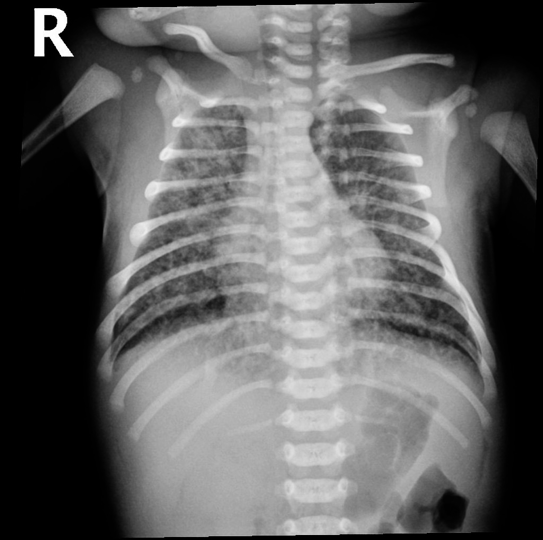

Pulmonary sequelae: Higher incidence of pneumonia, hyperinflation, consolidation, patchy infiltrates. If severe, air leak and pneumomediastinum may occur.

- Hyperinflation,

- Consolidation,

- Patchy infiltrates

- If severe, air leak and pneumomediastinum may occur